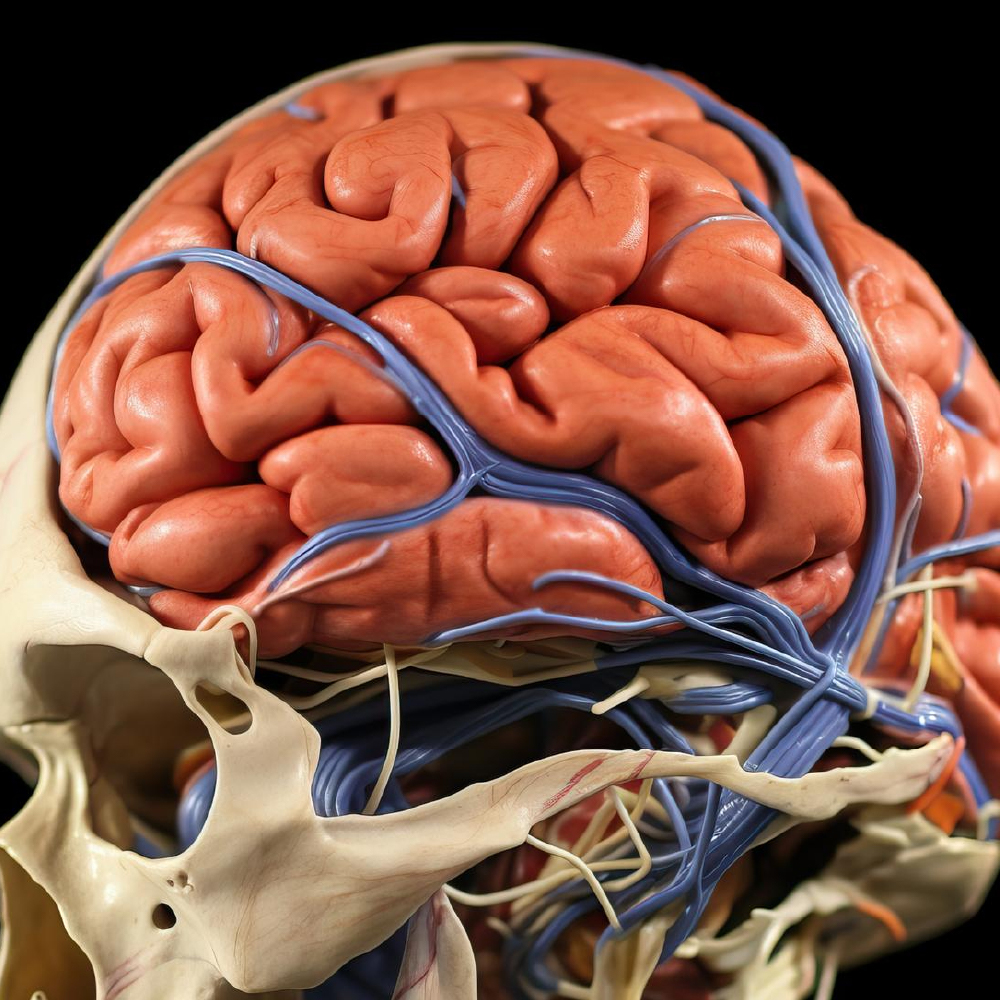

The project will focus on conducting in vivo epigenetic reprogramming experiments using nanoparticles (NPs) loaded with dCas9-VPR protein and specific gRNAs targeting human transgene promoters and neuronal reprogramming factors.

This involves inducing stab wound injuries in adult mice and delivering the NPs to the brain near the injury site via intracerebral administration.

The NPs will be activated by transcranial irradiation, and safety, localization, and epigenome editing capacity will be assessed over time.

Spatial transcriptomics will be performed to evaluate successful in vivo reprogramming of astrocytes into neurons.

Additionally, in vivo epigenetic reprogramming will be conducted using the most effective administration route of the NPs, and whole brain spatial transcriptomics will be performed to confirm any off-target events.

The Work Package 3 involves several activities related to the generation of reporter mice, epigenetic reprogramming of astrocytes, selection of the route of administration of nanoparticles (NPs), in vivo toxicity assays, and pharmacokinetic and pharmacodynamic studies.

These activities include the use of transgenic mouse lines to analyze and quantify formulation delivery in vivo, isolation and transfection of astrocytes with NPs containing dCas9-VPR protein and gRNAs targeting specific sequences, labeling of NPs with a Cy7 dye to measure accumulation in the brain, in vivo toxicity studies in mice to estimate the toxicological profile of the particles, and pharmacokinetic and pharmacodynamic studies to assess the distribution and effects of the epigenetic reprogramming formulation.